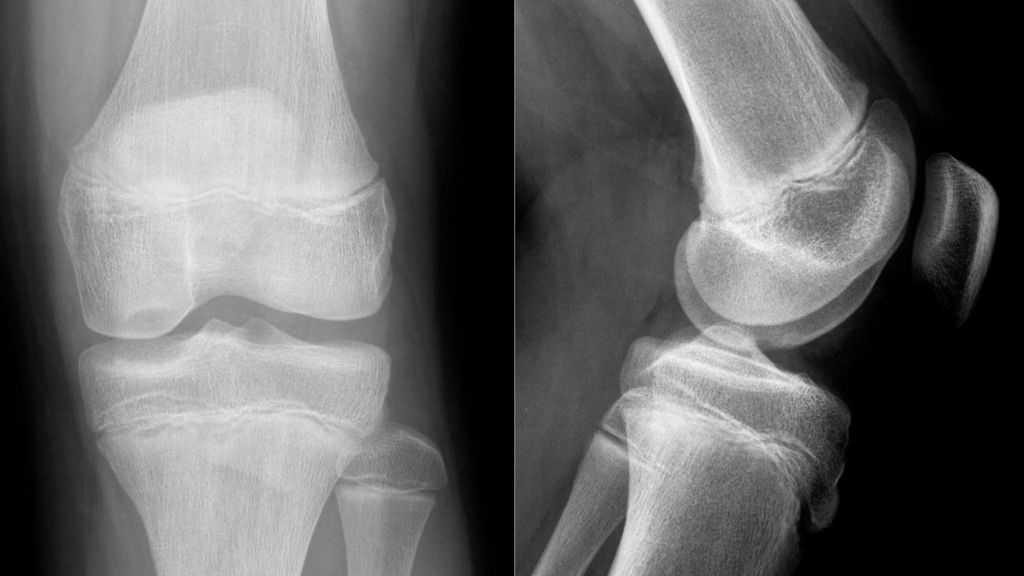

Abb. 4: 13-jähriger männlicher Patient mit einer instabilen Osteochondritis-dissecans-Läsion am posterolateralen medialen Femurkondyl präoperativ (A, D), 3 Monate (B, E) sowie 12 Monate (C, F) nach Refixation mittels Shark-Screw

Abb. 5:13-jähriger männlicher Patient mit einer instabilen Osteochondritis-dissecans-Läsion am posterolateralen medialen Femurkondyl präoperativ (A, C) sowie 12 Monate (B, D) nach Refixation mittels Shark-Screw